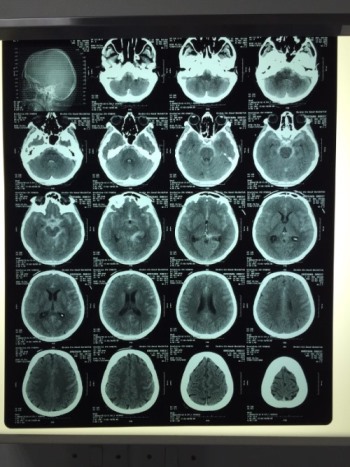

BOLNIČKI SNIMAK

Međutim, radost zbog ovog dolaska narušila je strašna vest: gospođa Brkić je nekoliko dana po dolasku u Dubai doživela izliv krvi u mozak. Hitno je hospitalizovana, ali kako nije imala zdravstveno osiguranje, troškovi bolničkog lečenja koje Svetlana i Miroslav moraju da plate su izuzetno veliki.

Gospođa Brkić je, zbog izuzetno teškog zdravstvenog stanja, morala da provede u bolnici dve sedmice, operisana je i lekari će ovih dana dati prognoze da li bi njen transport iz Dubaija u Srbiju bio moguć i bezbedan što pre. Naime, nju još hrane „preko cevčice“, a sadašnje lekarske procene su takve da gospođa Brkić ne bi mogla da provede let u sedećem položaju, što zbog ozbiljno narušenog zdravlja, što zbog komplikacija koje bi mogle da uslede tokom leta.